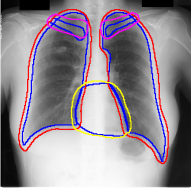

For each of these three datasets, we use three noise settings, denoted by , and . and are two settings synthesized by our Markov process with (expansion) and (shrinkage), respectively. Figure 4 shows examples of our synthesized label noise. We also include the mix of random dilation and erosion noise used by previous work (Zhu et al., 2019; Zhang et al., 2020b; a). This is achieved by randomly dilate or erode a mask with a number of pixels. Note that our Markov label noise can theoretically include this type of noise by setting . Detailed parameters for these settings are provided in the Appendix.

Real-world label noise. To evaluate with real-world label noise is challenging. We are not aware of any public medical image segmentation dataset that has both true labels and noisy labels from human annotators. Therefore, we use a multi-annotator dataset, LIDC-IDRI dataset (Armato III et al., 2015; Armato et al., 2011; Clark et al., 2013), and the coarse segmentation in a vision dataset, Cityscapes (Cordts et al., 2016). The LIDC-IDRI dataset consists of 1018 3D thorax CT scans where four radiologists have annotated multiple lung nodules in each scan. The dataset was annotated by 12 radiologists, and it is not possible to match an annotation to an expert. We use the majority voting as the true labels and the union of four annotations as noisy labels. We process and split the data exactly the same way as Kohl et al. (2018). Cityscapes dataset contains 5000 finely annotated images along with a coarse segmentation by human annotators that we use as the “noisy label”. We only focus on the ‘car’ class because (1) cars are popular objects and are frequently included in images; (2) the coarse annotation of cars is very similar to noisy annotation in medical imaging – they are reasonable distortions of the clean label without changing the topology. See Figure 4(c) for an example. The detailed settings of LIDC-IDRI and Cityscapes can be found in Appendix A.2.1.

Table 1 shows the segmentation results of different methods with synthetic noisy label settings on JSRT , ISIC 2017 and Brats 2020 dataset. Note that QAM cannot be applied to Brats 2020 dataset because their network is designed for 2D only. We compare DICE score (DSC) on testing sets (against the clean labels). For each setting, we train 5 different models, and report the mean DSC and standard deviation. In and , where biases show up in noisy labels, the proposed method outperforms the baselines by a big leap in total case. The compared methods, however, only work when little bias is included, like . is equivalent to setting in our Markov model, resulting in . We also test the proposed method on real-world label noise, results shows in Table 2. Figure 5 shows examples of label correction results. We provide more qualitative results in the Appendix A.4.